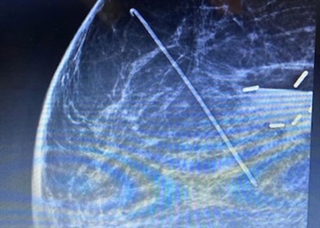

After a biopsy or tumor removal, the Accusyte fiducial sutures are sewn around the perimeter of the tumor bed at the anterior, posterior, middle, and lateral planes of the tumor cavity. The fiducials allow for accurate delineation of target volumes during treatment planning and assist with image guided radiation therapy (IGRT) before each session.

The fiducial markers are woven within an absorbable suture. When the body absorbs the suture, the fiducial markers remain within the tissue. Migration of the markers from their original position is unlikely, as the tissue produced during the healing process holds the markers in place. Sutures are sewn into place using the same technique as other sutures commonly used.

Accusyte 3-D Fiducial Marker Suture Set, 1 x 4 mm marker embedded into each suture. One box contains 6 sutures. One box per patient.